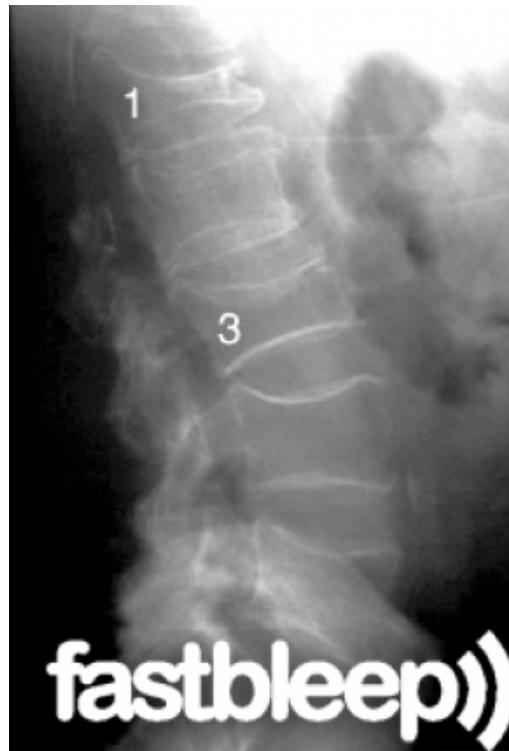

Osteoporotic Vertebral Compression Fracture

- Commonest vertebral injury

- Etiology: Minor trauma in osteoporotic people

- Prevalence: Affects up to 50% of people over 80 years old

- Diagnosis: Lateral radiographs

- Initial treatment: Observation and pain management

- Kyphoplasty: Reserved for patients with recalcitrant symptoms after 4-6 weeks of nonoperative treatment

- Diagnosis: Lateral radiographs; flexion and extension lateral lumbar radiographs can identify degree of instability